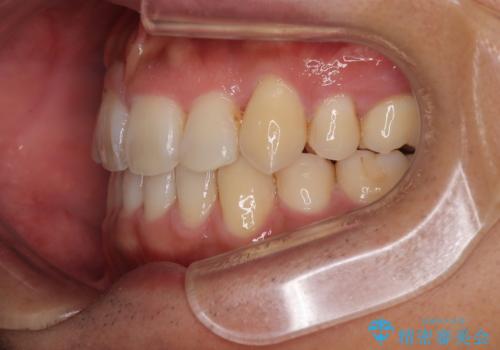

八重歯はきれいに整い、前歯もバランスよく収まり、横顔のラインも自然に改善されました。

治療後、患者様は「思い切り笑えるようになった」と大変喜んでくださいました。